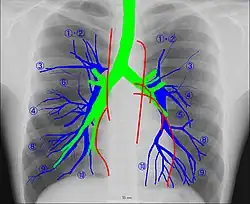

![[1][2]](./_assets_/Chest.jpg)

Human chest radiographic anatomy.

Human chest radiographic anatomy.

Radioanatomy (x-ray anatomy) is an anatomy discipline that involves studying anatomy through the use of radiographic films.[3] The x-ray film represents a two-dimensional image of a three-dimensional object due to the summary projection of different anatomical structures onto a planar surface.